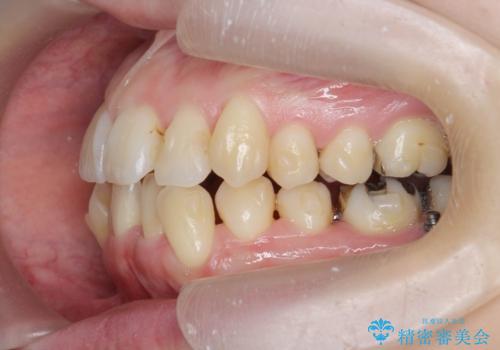

前歯のがたつき すれ違い咬合のマウスピース矯正治療

- 前歯のがたつきや歯の角度、矯正治療を希望され来院されました。

仕事の都合で、ワイヤー矯正を行うことが難しくマウスピース矯正であれば可能、という希望でした。

下顎が前にある咬合関係を可及的に咬合移動で改善し、IPR、下顎3前歯の仕上げで行うマウスピース矯正を計画します。